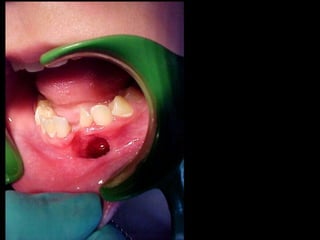

Eliminación de focos sépticos en bloque en paciente con osteitis

mandibular crónica

Osteomielitis

La osteomielitis es una infección súbita o de larga data del hueso o médula

ósea, normalmente causada por una bacteria piógena o micobacteria y

hongos. Los factores de riesgo son trauma reciente, diabetes, hemodiálisis y

drogadicción intravenosa.

La Osteomielitis se define como una inflamación extensa del hueso,

implicando a toda porción esponjosa, medular, cortical, periostio, vasos

sanguíneos, nervios y epífisis. La inflamación puede ser aguda, subaguda o

crónica y presenta un desarrollo clínico diferente según su naturaleza (1-5).

En el caso de los maxilares se considera la infección odontógena como la

causa más frecuente de osteomielitis. Se puede presentar a cualquier edad

con un predominio entre los hombres. Afecta principalmente al maxilar

inferior. En el maxilar superior es más raro, debido a una mayor

vascularización .